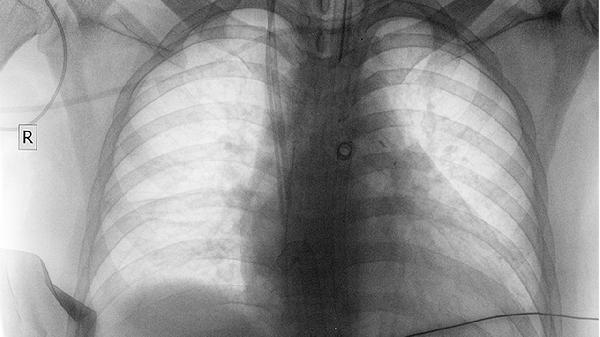

肺部膨脹不全可通過體位引流、呼吸訓(xùn)練、藥物治療、支氣管鏡治療、手術(shù)治療等方式恢復(fù)。肺部膨脹不全可能與支氣管阻塞、肺部感染、胸膜疾病、神經(jīng)肌肉疾病、外傷等因素有關(guān),通常表現(xiàn)為呼吸困難、咳嗽、胸痛等癥狀。

頑固性肺不張或合并膿胸時需行胸腔閉式引流或肺葉切除術(shù)。手術(shù)可徹底清除病灶,但創(chuàng)傷較大,術(shù)后需加強(qiáng)呼吸道管理。術(shù)前需評估心肺功能,術(shù)后早期下床活動預(yù)防深靜脈血栓,定期復(fù)查胸片觀察肺復(fù)張情況。